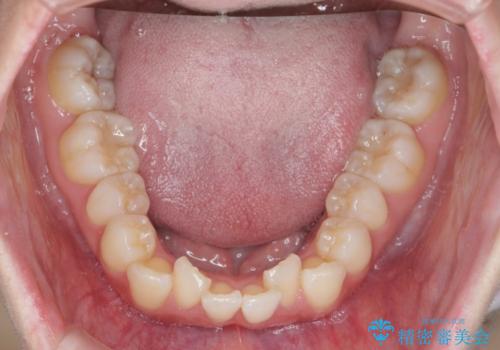

インビザラインで出っ歯の治療

- 「目立つ前歯の出っ歯をなんとかしてほしい。」と矯正治療を希望され来院されました。

突出した上顎の前歯に加え、ガタつきの目立つ下顎の歯列も同時にマウスピース矯正インビザラインで整えていきます。

突出間(所謂 出っ歯)のある前歯の位置は大幅に改善され、審美性が大きく向上しました。

加えて奥歯も噛み合わせも良くなったことで、咬合状態が安定しより安定した歯列を獲得することができました。